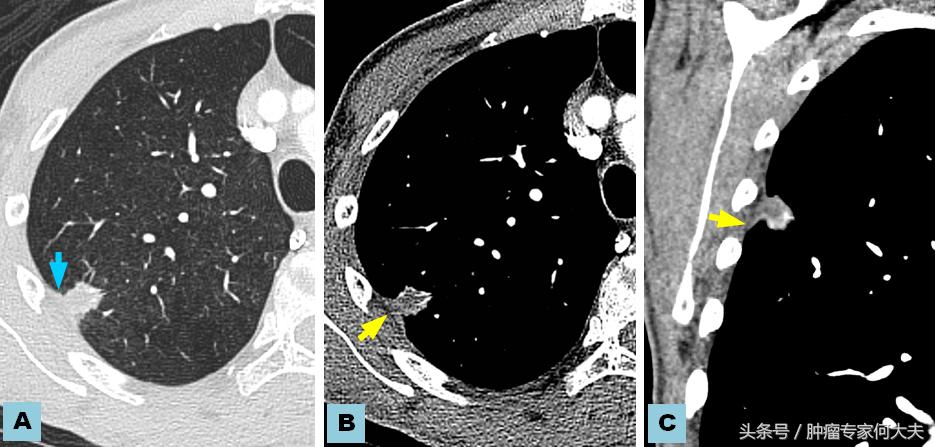

在第二年接近第三年的那次复查中,小豆被医生告知右肺也长了瘤子,医生建议小豆穿刺活检,小豆还是比较配合的,做了肺穿刺活检术,术后病理结果证实也是肺腺癌,和以前病理结果一样,医生推测可能是转移,并对取下的组织进行了基因检测,仍然没有检测到敏感突变基因,但医生建议小豆可以尝试口服“易瑞沙”,因为在生病的2年多时间里,小豆研读了很多肺癌的专业书籍,对肺癌的知识了解甚多,因此她同意了口服靶向药,在口服靶向药的两个月里,除过面部皮疹,没有其他不良反应,但用药三个月后,复查肺部CT,病灶依然没有明显变小迹象。医生考虑无效,于是就把靶向药停了。没有任何治疗,她还能撑多久?她自己不知道,医生们也众说纷纭,反正总体是时间不会太久,有的医生说也就半年一年左右,小豆说当时自己想“反正都这样了,与天争命也无济于事,静静等待未来会发生什么”。

就这样,读书、看报、上网,有时候和朋友出去游游逛逛,虽然癌症在身,她不能积极作为,只能听天由命,但是半年过去了,右肺出现的病灶生长势头不明显,一年过去了,两年过去了,三年过去了,一直在复查,但是复查的结果总是说变化不显著。但医生仔细对比三年之初与三年之末(最近)的片子,瘤子是有所长大,但都长的不算多,个别小病灶甚至自然变小。 最近,小豆说自己喘的明显了,夜里咳嗽厉害,难以成眠,要来查查,我给做了胸部CT检查,结果提示两肺多发占位病变,对比了她3年前刚发现右肺时的片子,这次明显变大,目前尚未做出诊疗计划。但对于小豆这样的病人,实属少见。人类对于肿瘤的认识仍然处于很原始的阶段。就拿肺癌来说,现代医学研究算是比较成功的一种瘤种,已经认识到一部分肺癌患者因为存在某些基因突变可以从治疗中获益,但是没有突变的患者并不是一定就很危险,个体差异相当大。希望每个人不要因为得了肿瘤,就自暴自弃。